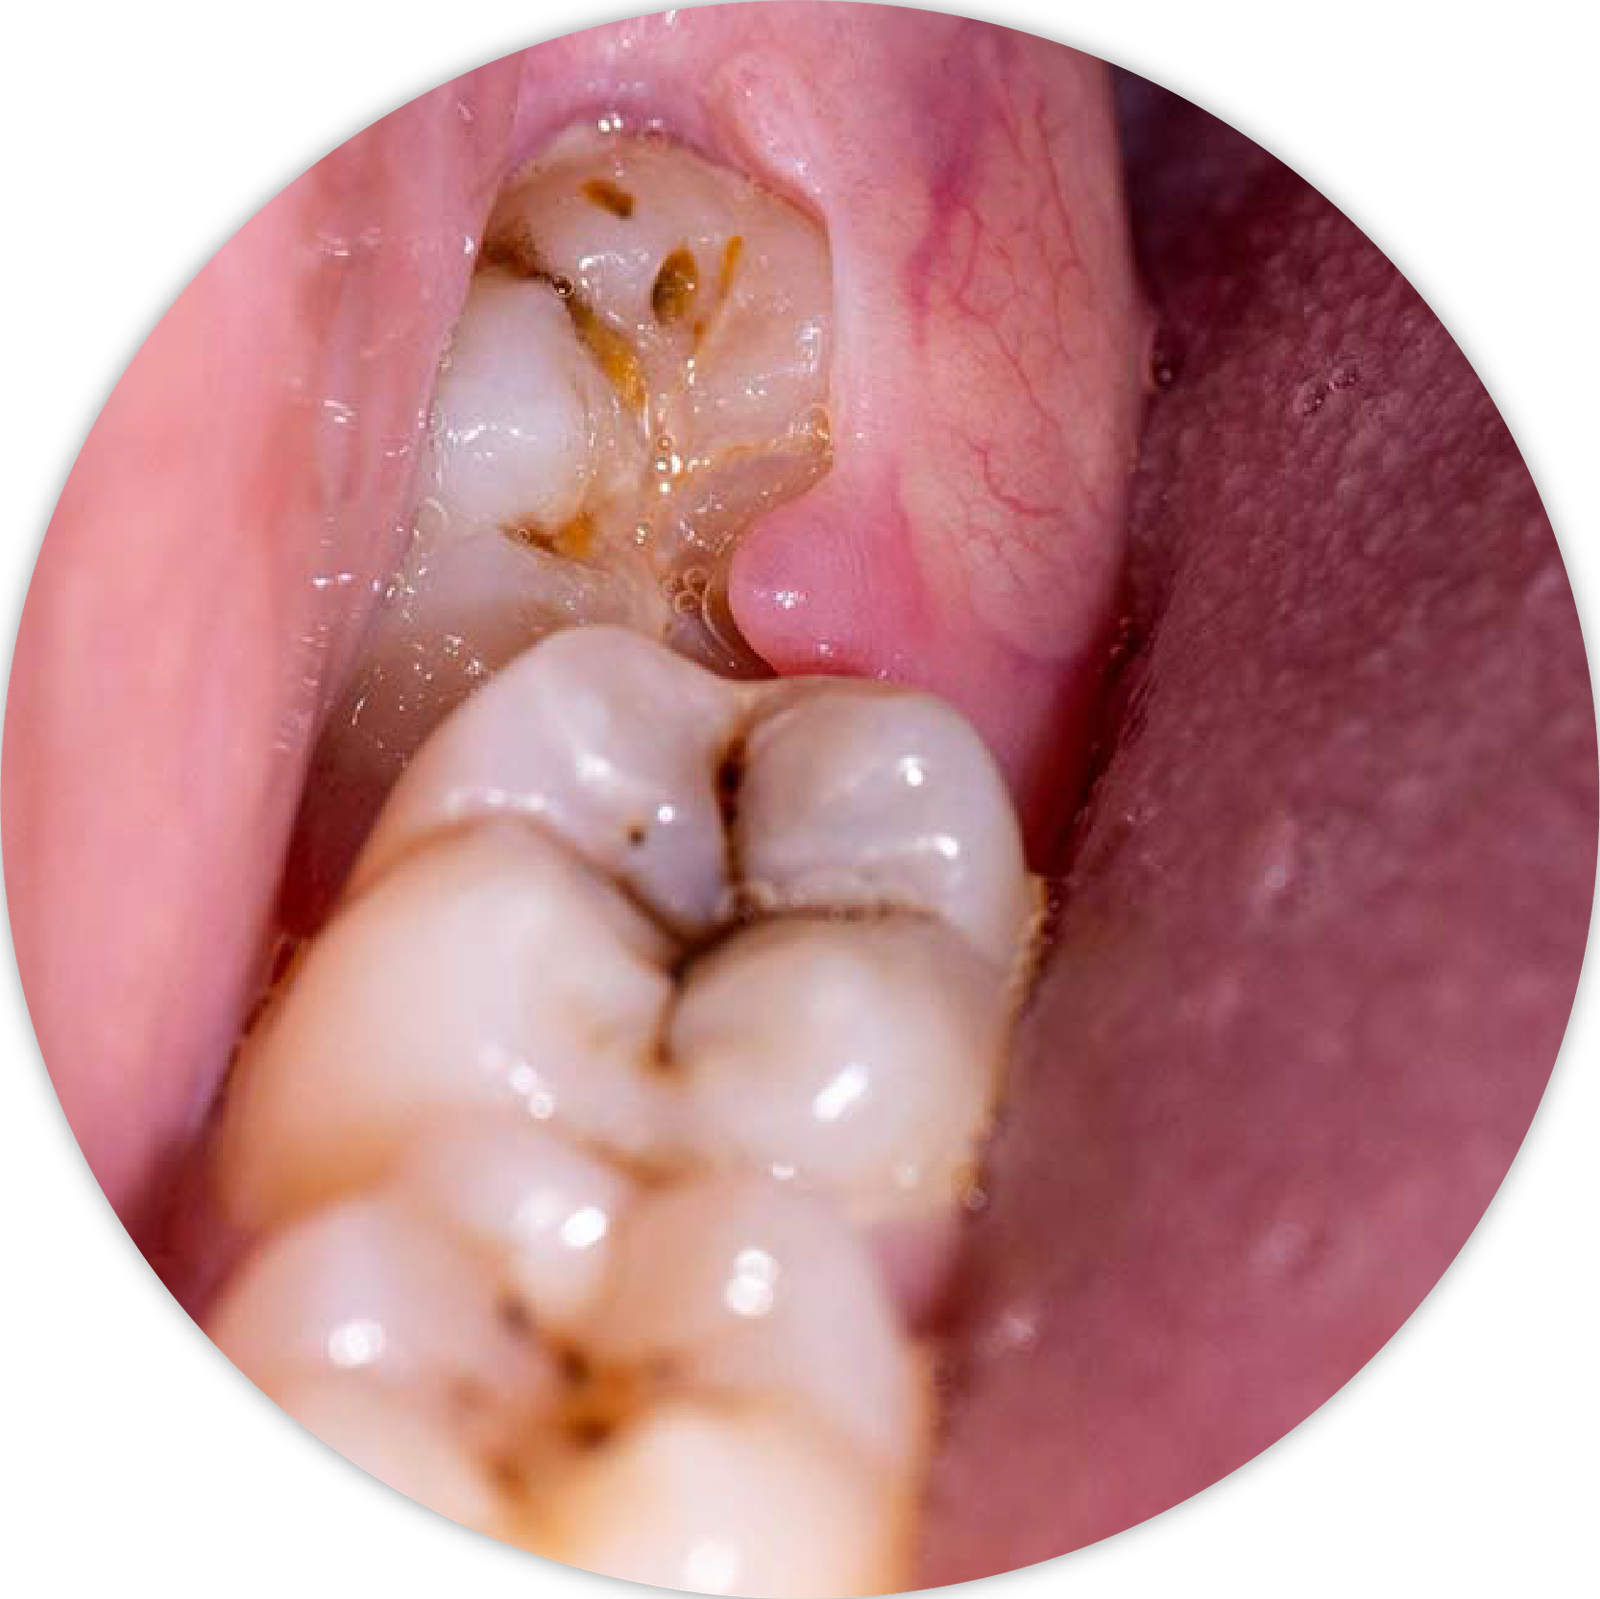

Răng khôn hay còn gọi là răng số 8, là những chiếc răng mọc ở phía trong cùng hai hàm răng ở những người trưởng thành trong độ tuổi trung bình từ 17- 25. Vì cấu trúc xương hàm người Việt chúng ta thường nhỏ, răng khôn không có đủ chỗ để mọc thẳng, dẫn đến tình trạng mọc lệch, mọc 1 phần, đâm xiên vào răng bên cạnh. Điều này dẫn đến nguy cơ kẹt thức ăn, viêm nướu, sâu răng, áp xe hoặc thậm chí là sưng viêm 1 bên mặt. Chúng tôi khuyến nghị khách hàng nên đi nhổ răng khôn từ giai đoạn răng mới mọc nhằm tránh các biến chứng và cơn đau.